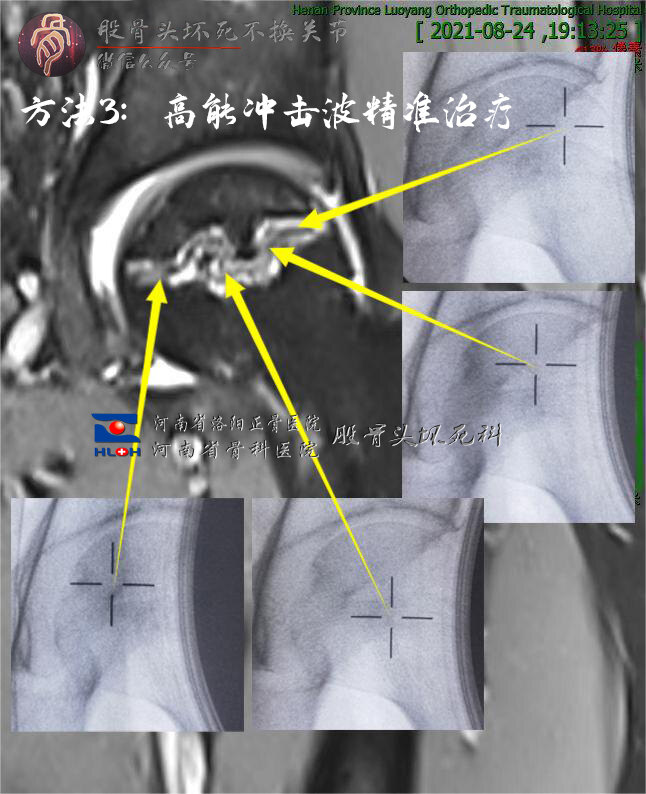

3. 当然,有条件的也可以行体外冲击波治疗,无创不手术,一周内见效,不影响工作,日常生活照旧,无需卧床休养、拄拐保护:

作为国内较早成立的股骨头坏死专科,我们采用了上述第3种方法,辅以中西药物治疗,患者无需长期卧床、拄拐,边工作边治疗,很快症状得到缓解,复查资料如下:

与治疗前比较,磁共振显示的“ 双线征 ”信号减弱、宽度变窄,再继续观察、间断治疗,股骨头无忧矣!